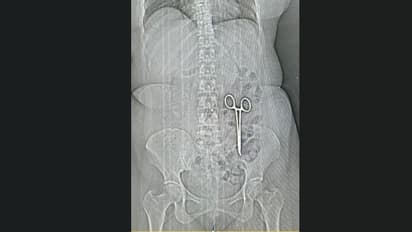

ഭോപ്പാൽ: കഠിനമായ വയറുവേദനയുടെ കാരണം കണ്ടെത്താൻ സിടി സ്കാൻ ചെയ്ത യുവതി ഞെട്ടിപ്പോയി. വയറ്റിനുള്ളിൽ കണ്ടെത്തിയത് ശസ്ത്രക്രിയയ്ക്ക് ഉപയോഗിക്കുന്ന കത്രികയാണ്. മധ്യപ്രദേശിലെ ഭിന്ദിൽ നിന്നാണ് ഡോക്ടർമാരുടെ അശ്രദ്ധയുടെ മറ്റൊരു റിപ്പോർട്ട് കൂടി പുറത്തുവന്നത്.

തുടർച്ചയായ വയറുവേദനയ്ക്ക് ഡോക്ടർ കുറിച്ച് നൽകിയ മരുന്നുകളൊന്നും ഫലിക്കാതെ വന്നതോടെയാണ് കമല ബായ് എന്ന 44കാരി സ്കാൻ ചെയ്തത്. അപ്പോഴാണ് കത്രിക കണ്ടെത്തിയത്. വയറ്റിൽ ലോഹവസ്തുവാണ് ആദ്യം കണ്ടതെന്നും പിന്നീടത് കത്രികയാണെന്ന് തെളിഞ്ഞതായും സ്കാൻ ചെയ്ത സതീഷ് ശർമ പറഞ്ഞു.

രണ്ട് വർഷം മുമ്പ് ഗ്വാളിയോറിലെ ഒരു ആശുപത്രിയിൽ കമലയ്ക്ക് ശസ്ത്രക്രിയ ചെയ്തിരുന്നുവെന്ന് കുടുംബം പറയുന്നു. അന്നു മുതൽ നിരന്തരം വയറുവേദന അനുഭവപ്പെട്ടു. മരുന്ന് കഴിച്ചിട്ടും മാറ്റമുണ്ടാകാതിരുന്നതോടെയാണ് സ്കാൻ ചെയ്യാൻ ഡോക്ടർമാർ നിർദേശിച്ചത്. ശസ്ത്രക്രിയയ്ക്കിടെ ഡോക്ടർമാർ അബദ്ധത്തിൽ കത്രിക വയറിനുള്ളിൽ മറന്നതാണെന്നാണ് സംശയം.